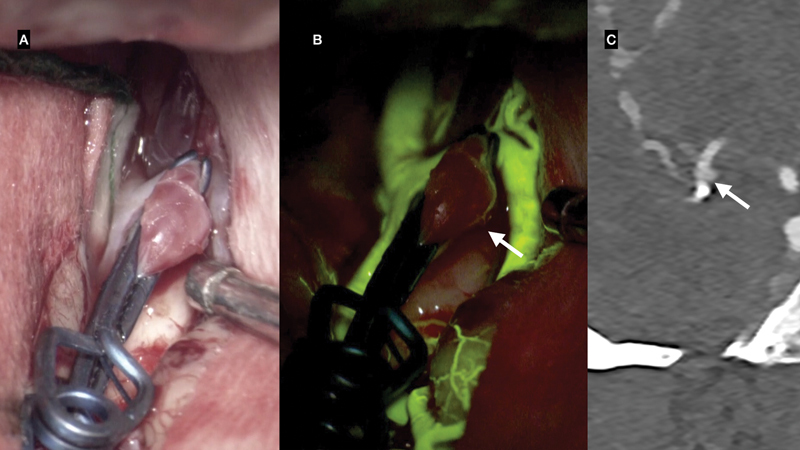

Results: FL-VA showed complete occlusion in 57 out of 61 aneurysms (93.4%), with 10 cases of discordance identified in postoperative CTA. One patient showed a neck remnant in FL-VA, but CTA revealed a residual aneurysm. Another patient displayed neck remnant and stenosis in branching vessels on CTA, not identified by FL-VA. Additionally, five aneurysms had neck remnants, and three had stenosis in branching vessels, detected in CTA but missed in FL-VA. Statistical analysis did not reveal significant associations between discordance and studied factors.